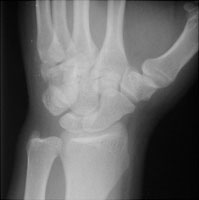

Hamate Fracture

Fractures of the hamate are rare and mostly occur with in association with other injuries, often with dorsal dislocation of the fourth and fifth metacarpals or a triquetral fracture. A fracture of the base of the hamate hook is rare and requires special views.

- Click on the image for a larger versionBOblique radiograph of the wrist. This shows a fracture of the body of the hamate.